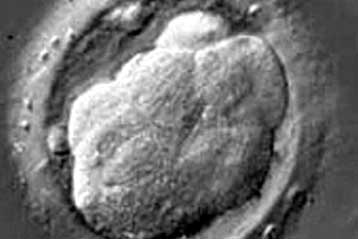

Σημαντική μείωση στα περιστατικά καρκίνου στον τράχηλο της μήτρας αναμένεται να φέρει το πρώτο εμβόλιο κατά των κονδυλωμάτων, του συχνότερου αφροδίσιου νοσήματος. Το Gardasil της Merck & Co. Inc εγκρίθηκε στις ΗΠΑ για χρήση σε κορίτσια από εννέα ετών.